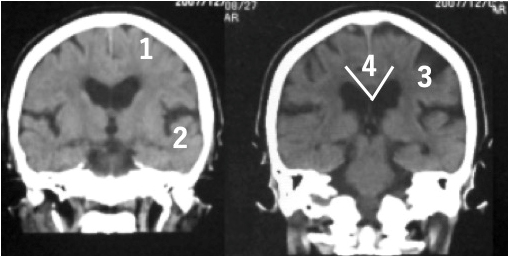

特発生正常圧水頭症のCT画像

特発生正常圧水頭症の特徴的CT所見(通常は脳を水平に撮影しますが、冠状に撮影した画像のほうがより特徴を捉えることができます)

- 脳の上のほうの隙間が狭い

- 前頭葉と側頭葉の隙間が大きく開く

- 局所的に大きな脳の隙間がある

- V字型になる(正常では直線に近い)